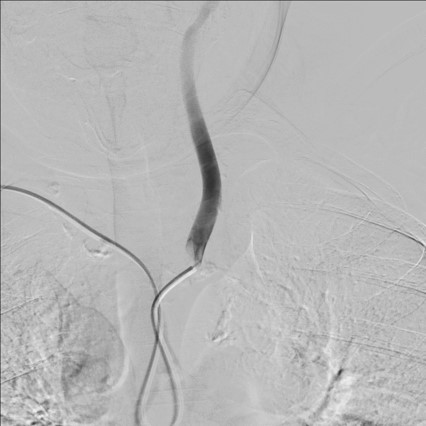

导管超选择左锁骨下动脉